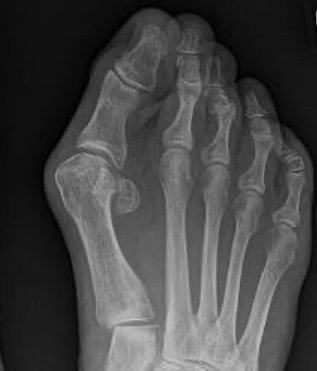

Mann Classification

1. Congruent

2. Incongruent - mild / moderate / severe

3. Degenerative

Incongruent

| Mild | Moderate | Severe |

|---|---|---|

|

HVA < 30° IMA < 15° Lateral sesamoid < 50% uncovered |

HVA 30 - 40° IMA 15 - 20o Lateral sesamoid 50 - 75% uncovered |

HVA > 40° IMA > 20° Lateral sesamoid > 75% uncovered |